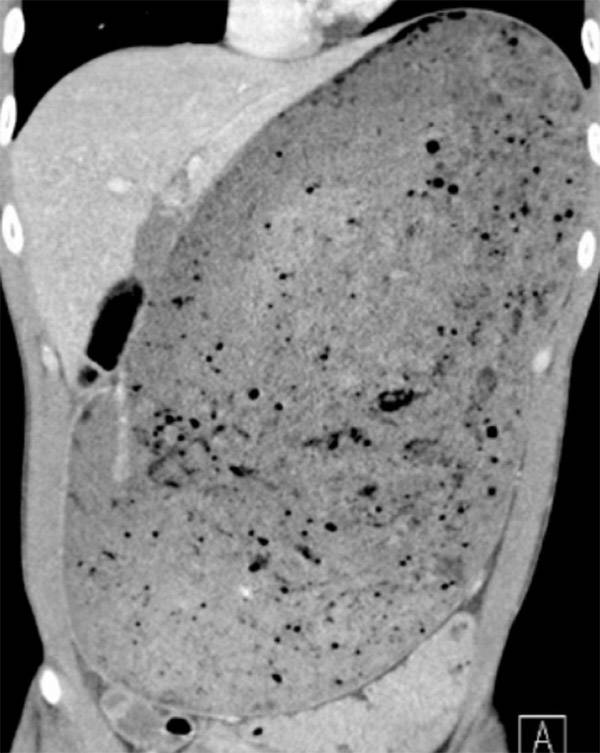

싱가포르 국립대 응텡펑 종합병원 의료진은 “이렇게 위가 너무 많이 늘어나면 혈류가 차단돼 파열을 유발할 수 있다”며 “소화되지 않은 음식물이 복부로 누출돼 감염이나 장기 부전의 위험까지 일으킬 수 있다”고 경고했다. 실제 남성의 복부 CT 사진에는 배꼽 바로 위부터 어깨 부근까지 위가 음식물로 거대하게 팽창해 있는 모습이 고스란히 담겼다.